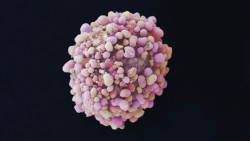

La cirugía es un tratamiento viable para los pacientes con cáncer de páncreas, especialmente tras la quimioterapia

Los pacientes con cáncer de páncreas en estadio II que reciben quimioterapia seguida de una intervención para eliminar la parte cancerosa del órgano, viven casi el doble de tiempo que los pacientes que reciben quimioterapia sola, según una nueva investigación publicada en línea en el `Journal of the American College of Surgeons`.